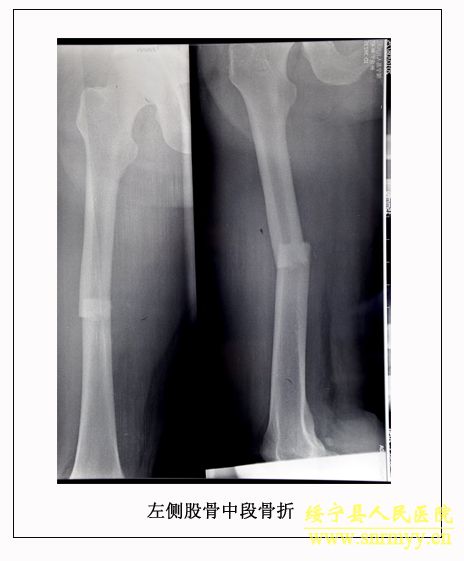

经检查:当时病人体温36.5℃、脉搏105次/分钟、呼吸25次/分钟、血压152/98mmhg,呈昏迷状,头面部、右手、左下肢均不同程度受伤,双侧瞳孔不等大,光反射消失;同时右手臂和左大腿均有骨折。GCS评分:仅4分,根据评分标准(轻度颅脑损伤为12—15分、中度为8—12分、重度为5—8分、极重度为3—5分)该病人属于极重度颅脑损伤。CT检查结果为脑干挫裂伤、双侧额叶、左颞叶、右顶叶脑挫裂伤、左侧颞部硬膜外、下血肿,左顶硬膜下血肿,蛛网膜下腔出血,脑室内积血,左侧额部下积液,左眼框内侧壁,枕骨骨折。X光片显示右桡骨粉碎性骨折,左股骨干骨折。诊断为:1、极重度颅脑损伤:(1)脑干挫裂伤。(2)双侧额叶、左颞叶、右顶叶脑挫裂伤。(3)右颞部硬膜外血肿。(4)外伤性蛛网膜下腔出血。(5)枕骨骨折。(6)头皮多处挫裂伤。2、右桡骨粉碎性骨折。3、左股骨干骨折。临床上如此严重的脑损伤死亡率极高,再加上合并多处骨折创伤,病人危在旦夕。

经再次检查,病人的身体状况明显好转,但意识模糊。9月28日,病人意识逐渐清楚。为方便护理,让病人早日康复,由沈建辉副院长亲自主刀,刘兴淼医师为助手,为病人实施了左股骨开放复位和交锁髓钉内固定术。10月21日,病人生活基本能自理,近日即可出院。 (2010.10.26)